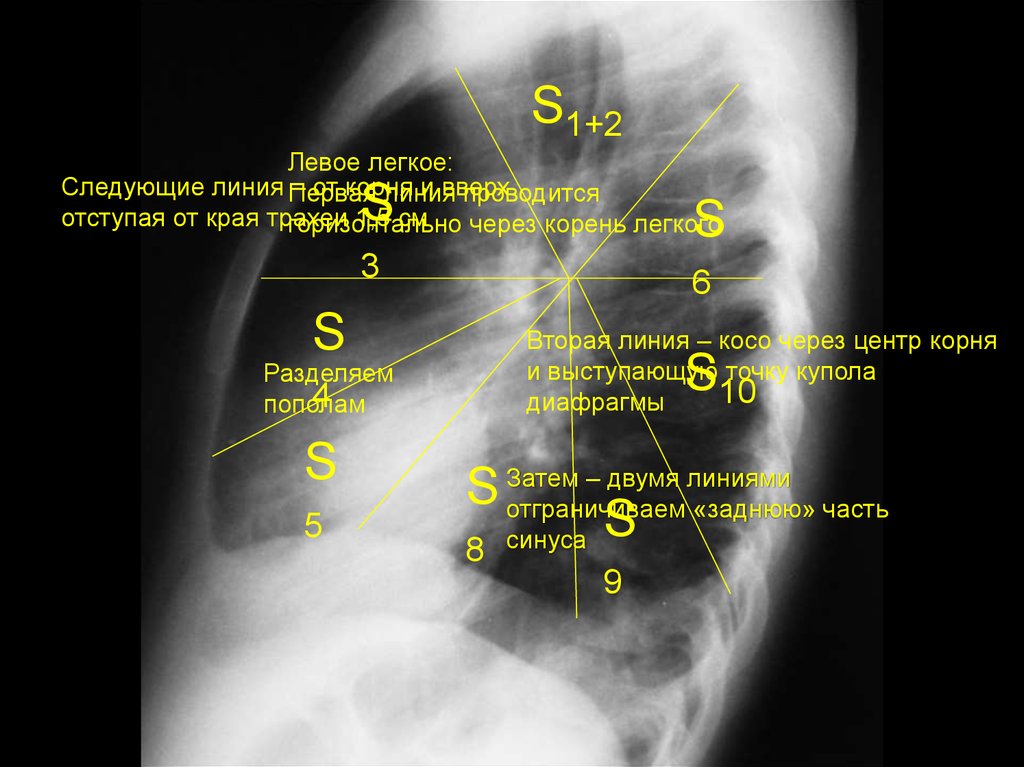

4.

S1+2

Левое легкое:

Следующие линия Первая

– от корня

и вверх

линия

проводится

отступая от края трахеи

1,5 см

горизонтально

через корень легкого

S

3

6

Разделяем

4

пополам

5

Вторая линия – косо через центр корня

и выступающую точку купола

10

диафрагмы

– двумя линиями

S Затем

отграничиваем «заднюю» часть

синуса S

8

9